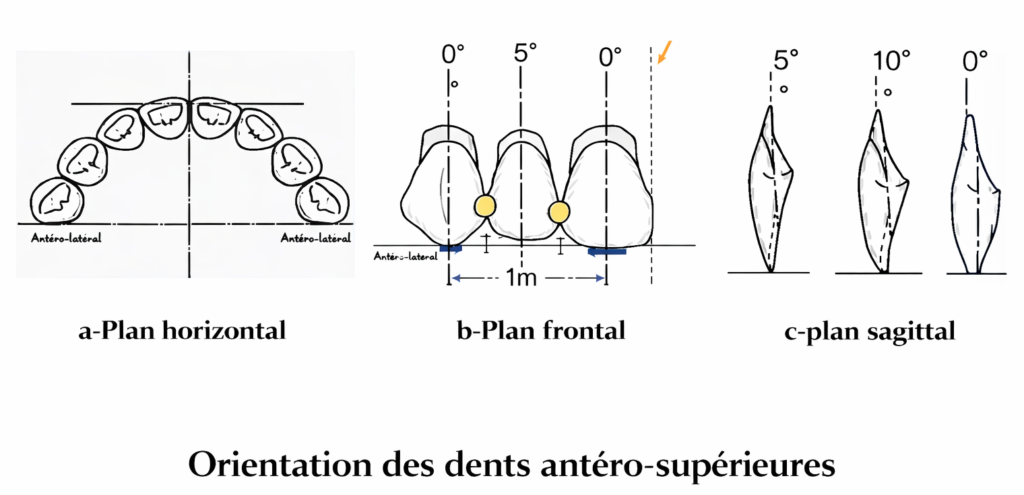

Orientation des dents antéro-supérieures

L’incisive centrale supérieure

Plan horizontal :

Le bord libre se situe à environ 6 à 8 mm en avant de la papille rétro-incisive.

Plan frontal :

Les deux incisives centrales se situent de part et d’autre de la ligne médiane, leur grand axe est parallèle à cette ligne. Le bord libre est en contact avec le plan d’occlusion.

Plan sagittal :

Le collet sera légèrement lingualé de 5° par rapport à la perpendiculaire.

L’incisive latérale supérieure

Plan horizontal :

Son bord libre suit la courbe amorcée par l’incisive centrale, il peut être légèrement en retrait.

Plan frontal :

Son axe est légèrement distal de 5°. Le bord libre est situé plus haut que le plan d’occlusion prothétique de 1 mm.

Plan sagittal :

Le collet sera lingualé de 10° par rapport à la verticale.

La canine supérieure

Plan horizontal :

Les pointes des deux canines sont reliées par une droite qui passe par le centre de la papille rétro-incisive.

Plan frontal :

L’axe de la canine est droit, parallèle à celui de l’incisive centrale supérieure. La pointe de la canine est en contact avec le plan d’occlusion.

Plan sagittal :

Pas d’inclinaison, le grand axe est droit.